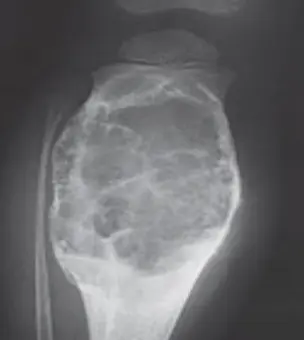

-

14-year-old patient with pain and swelling at lower right thigh

- Most important X-ray findings: Sun ray appearance, Codmanโs triangle

- Diagnosis: Osteosarcoma

14-year-old patient complaining of pain and swelling at lower R thigh

- Findings: Codmanโs triangle, Sun burst appearance

Codman trinagle